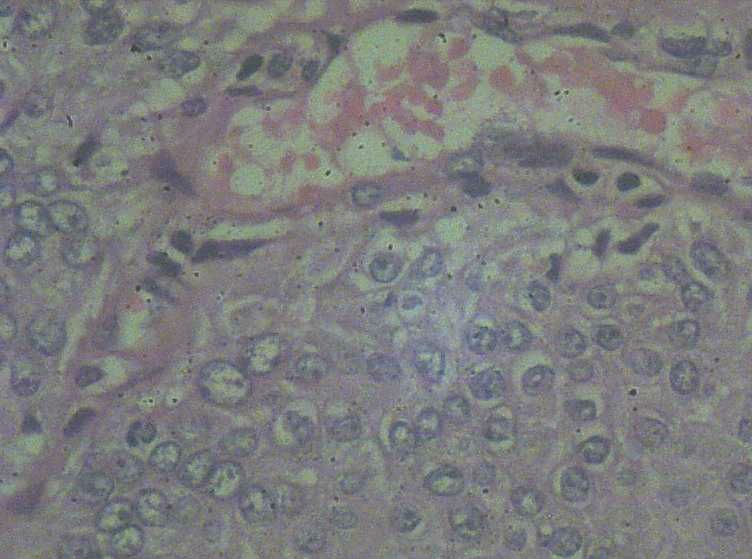

33岁 宫颈刮片看上去很像腺上皮病变,报了AGC 建议活检。 活检取自宫颈,图片如下:请帮忙看下,谢谢!

鳞状上皮增厚,乳头状增生,并见挖空样细胞。提示HPV感染。

有不典型增生, 不知道大家有没有看到。  如果有不典型和上面的图像可或直接报 :尖锐湿疣伴不典型增生。